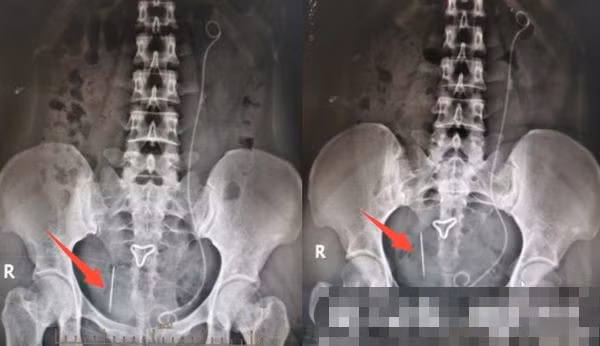

| Phim chụp của cô Tiễn. |

Khi siêu âm ổ bụng cho cô Tiễn, ngoài bóng sỏi, các bác sĩ còn phát hiện ra một cây kim dài khoảng 3cm ở phía sau miệng ngoài cổ tử cung. Giật mình, bác sĩ hỏi cô Tiễn đã từng nuốt phải vật gì lạ hay không.

Hẹn sau 2 ngày đi khám lại, bác sĩ phát hiện kim vẫn bị dịch chuyển. Nếu không phẫu thuật ngay để loại bỏ thì chiếc kim có thể xuyên trực tiếp vào phúc mạc và làm thủng ruột, gây rò rỉ ruột, thậm chí làm thủng các mạch máu lớn và gây xuất huyết.